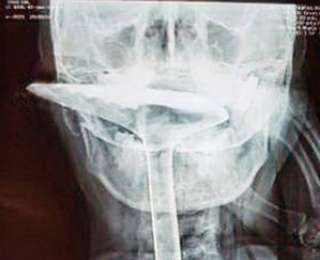

Чтобы спастись, женщина пробила горло кухонной лопаткой длиной 30 см. Обратно ее доставали уже врачи. Хирургам пришлось удалить часть горла из-за серьезных повреждений, но в остальном с дамой все будет в порядке.